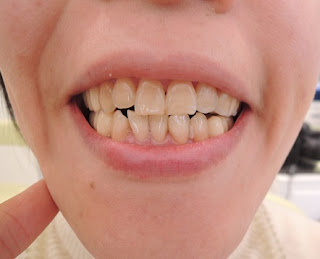

既に上下臼歯部は全てTEKに置き換わっていることや、これまでの他院での治療などが原因で最低限の侵襲でということで、シェルタイプで誘導することになりました。

適合を確認し、さっそく接着します

接着後、チェアーを倒している状態での「噛んでください」のときです

全く咬みません

座位での「噛んでみましょう」の図です

「では、もう少し前で噛んでみましょう」の図です

「大丈夫そうです」と、患者さん

現段階では左側は咬合紙が抜けます

というか、目に見えて咬んでいません

患者さんに具合を伺うと、「説明していただいたことが凄く良く分かります、大丈夫そうです」だそうです。

後日両側のバイト状態を確認しながら、状態を観察できればと思っています。

そのときは、偏位に対する本人の受け入れ具合の確認に合わせて、ダイレクトボンディングによる犬歯誘導の確立をしてもらい、次のステップへ移行する予定です。